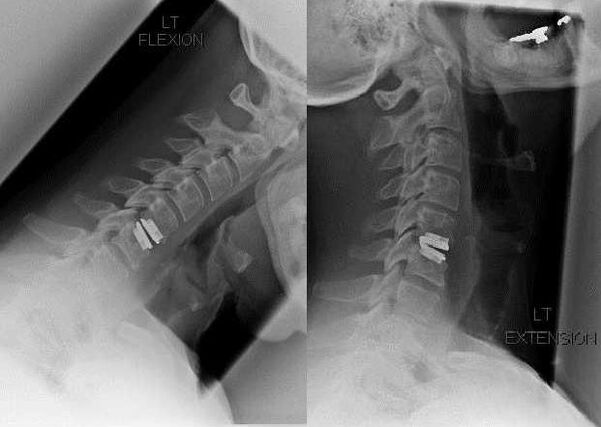

Surgical intervention

Indications for surgical intervention include ineffectiveness of conservative treatment, as well as complications of cervical osteochondrosis, for example, discogenic myelopathy, vertebral artery syndrome and radicular syndrome.The following operations are performed to decompress the spinal cord, blood vessels and spinal roots:

- laminectomy;

- laminotomy;

- foraminotomy;

- facetectomy;

- discectomy.

During surgery, bone fragments and ligaments may be cut, and the intervertebral discs may be completely or partially removed.For small herniated protrusions, laser vaporization of the disc core is often performed.

After excision of the vertebral structures, stabilization of the mobile segments of the spine is often required by spinal fusion or the installation of bone and dermal autografts.